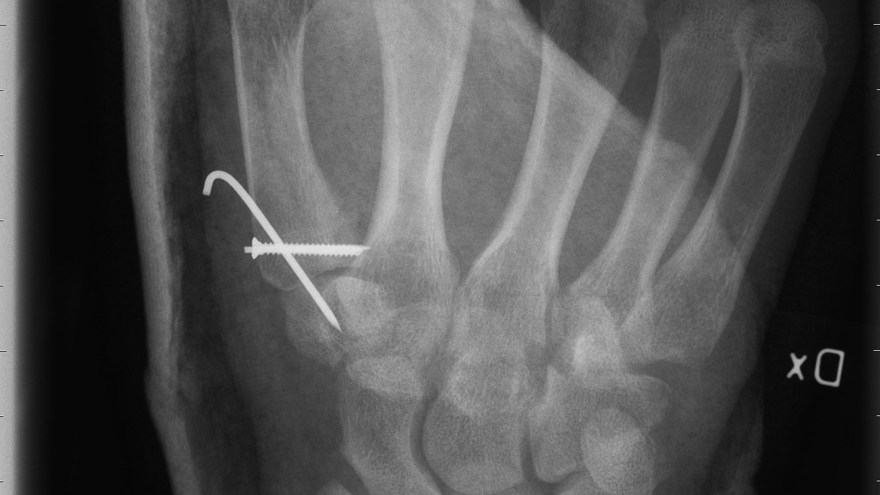

Bennetfraktur

Bennetfraktur är en intraartikulär luxationsfraktur genom basen av metacarpale I. Metacarpalbasen tenderar att luxera genom APL senans dragning i radiell-proxmal riktning. Frakturen behöver därför i princip alltid reponeras och immobiliseras internt med stift. Kan se väldig beskedlig ut på primära bilder men dislocerar succesivt genom senans dragning – klassificeras därför som ”lurig”.

Mekanism vid Bennetfraktur

Bennetfraktur där det ulnara fragmentet i basen på metkarpalen hålls kvar med hjälp av ligament i karpus. På grund av drag i abductor pollicis longus (APL) uppstår nästan alltid en diastas i frakturen. Diastasen i ledytan ger sekundärt artros. Dessa frakturer kräver således exakt fixation – vanligen i form av stift eller skruv.